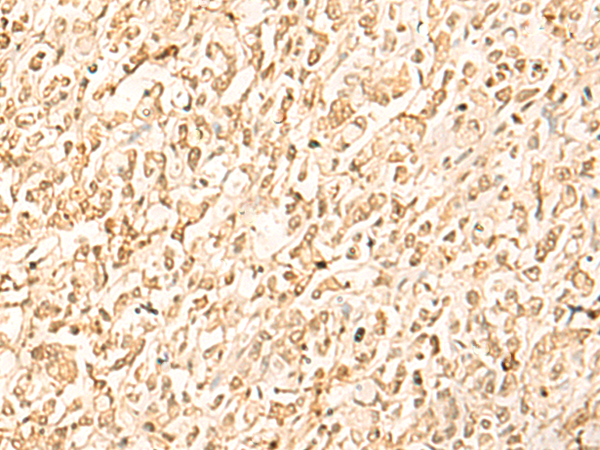

分类: 科研抗体货号: P04091别名: MEK2, MKK2, MAPKK2, PRKMK2应用: WB,IHC反应种属: Human, Mouse, Rat